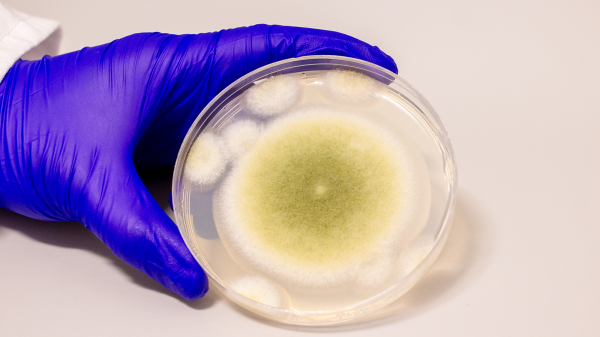

Грибок, який, можливо, спричинив «прокляття Тутанхамона», демонструє потенціал у лікуванні раку